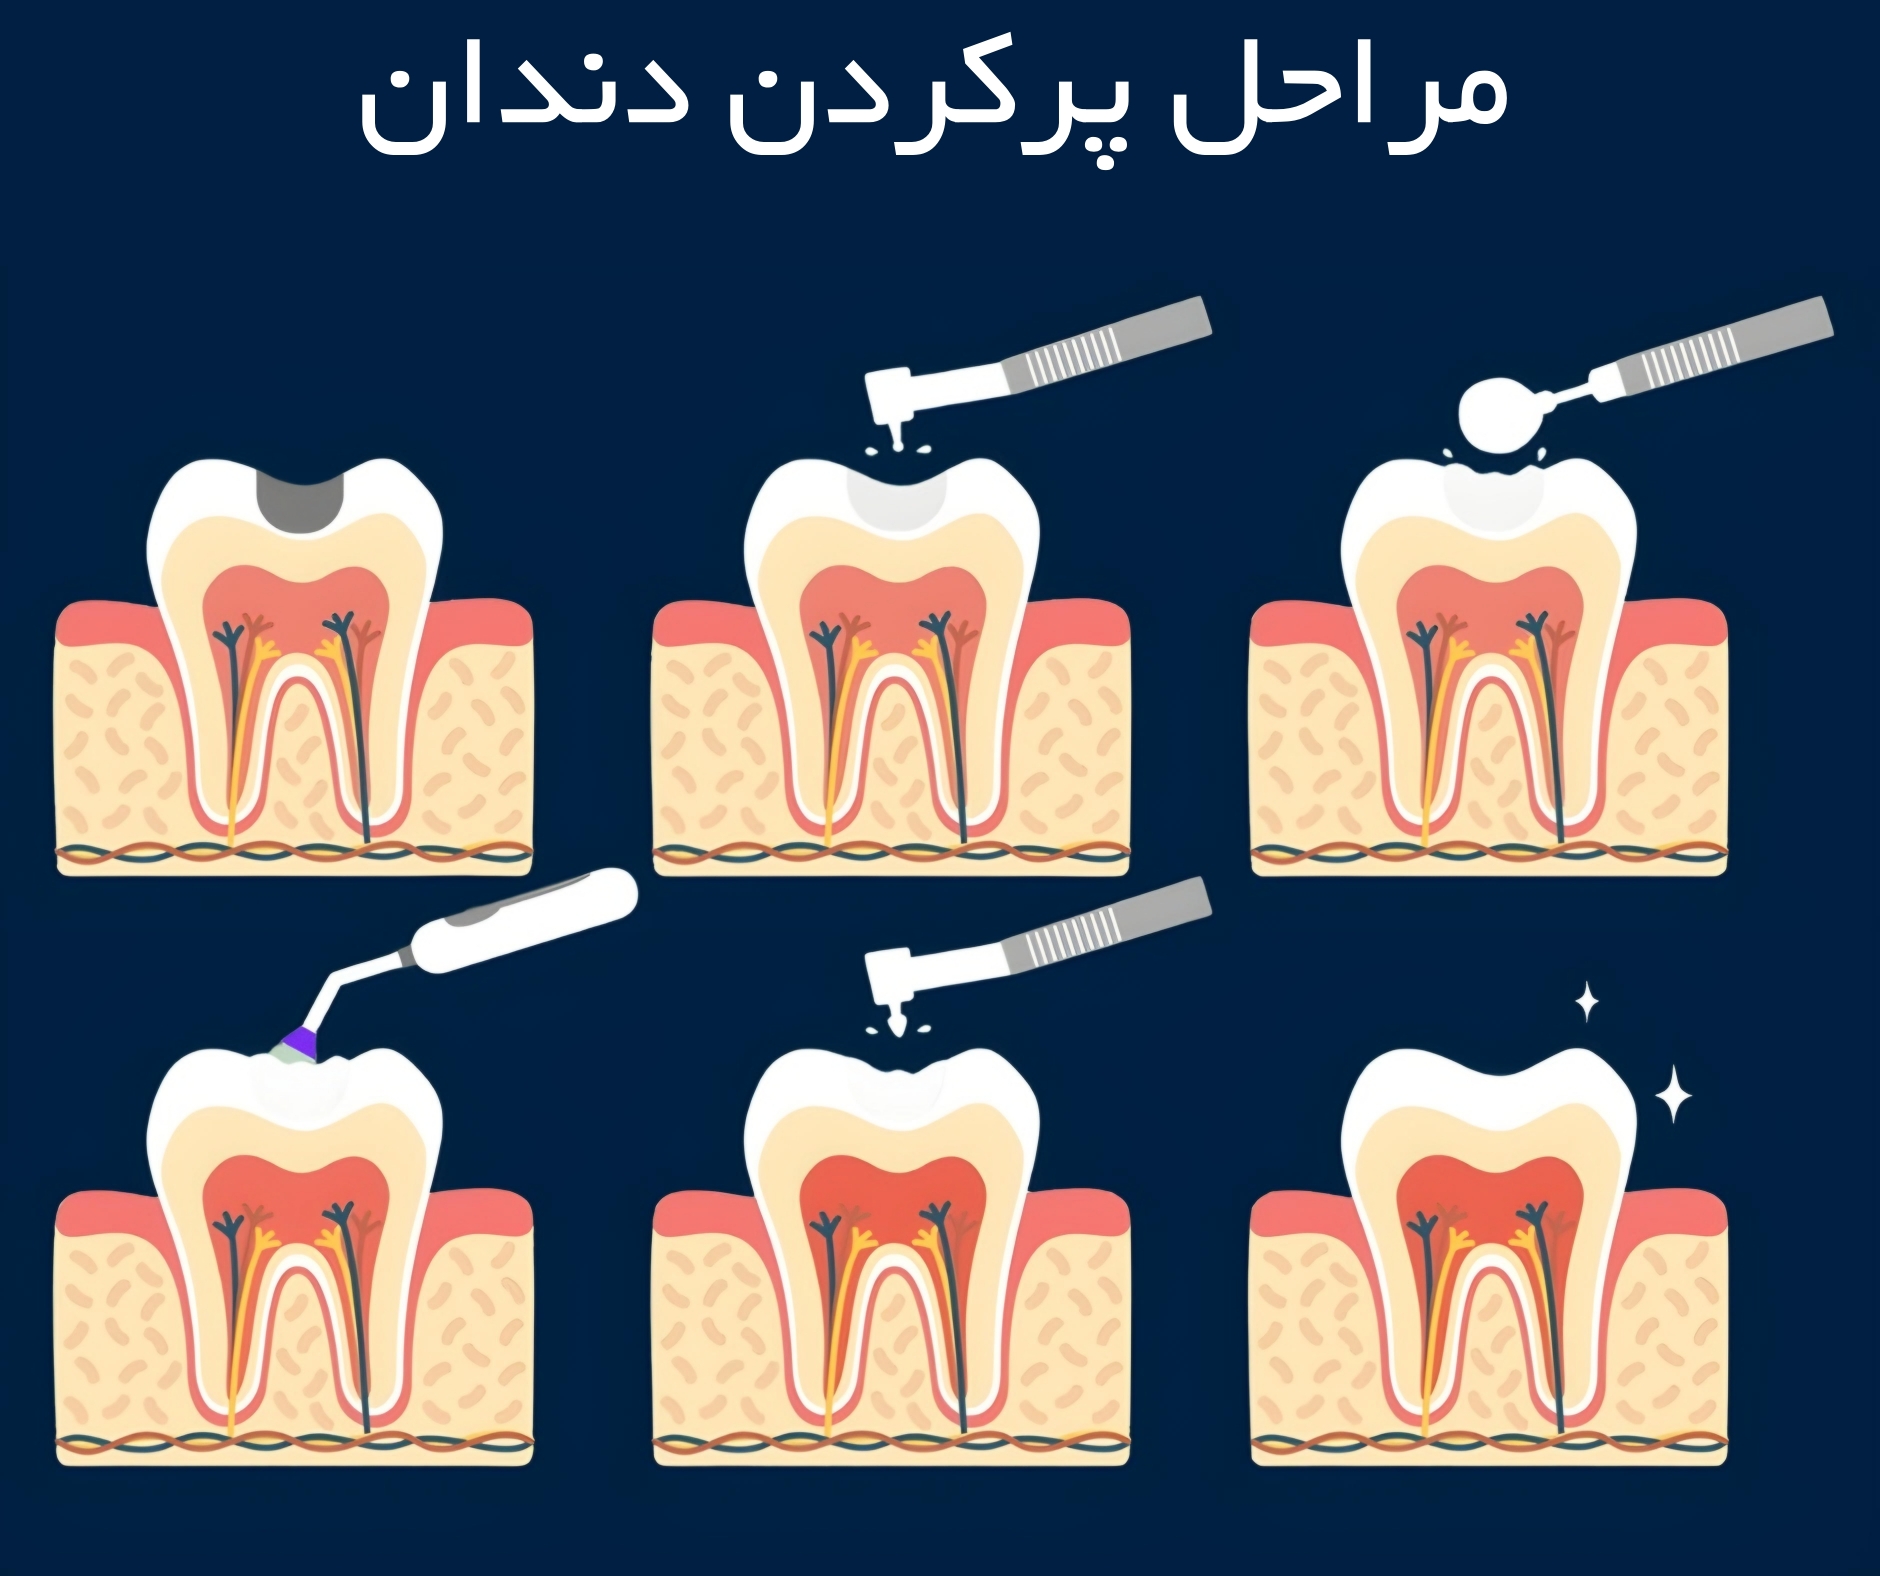

فرآیند و مراحل پر کردن دندان

دندانپزشک در ابتدا دندان و ناحیه اطراف را برای ترمیم قسمت آسیب دیده آماده و تراش میدهد. پوسیدگی یا آسیبدیدگی با لیزر یا هندپیس دندانپزشکی برداشته شده و جرمگیری این ناحیه برای پاک سازی از باکتریها یا ذرات باقیمانده پیش از تکمیل ترمیم انجام میشود.

برای پر کردن دندان با کامپوزیت ابتدا می بایست دندان پوسیده را ایزوله نمود. ایزوله کردن دندان پوسیده در ترمیم با کامپوزیت به این دلیل بسیار مهم است که اجازه نمیدهد رطوبت درمان باندینگ را با اختلال مواجه کند. دندانپزشک در باندینگ لایههای چسب و سپس ماده کامپوزیت را روی دندان میزند و آن را با تابش نور مخصوص خشک و سفت میکند. این نوع درمان زیبایی خاص خود را به همراه دارد.

مراحل و نحوه پر کردن دندان با ماده کامپوزیت

1. متخصص دندانپزشک ابتدا دندان تحت درمان را ایزوله میکند تا بزاق به آن راه نداشته باشد و دندان خشک باقی بماند.

2. سپس با استفاده از دریل دندانپزشکی قسمت هایی که پوسیده و عفونی شده اند، برداشته می شوند.

3. رزین کامپوزیت به صورت لایه لایه در فضای خالی ایجاد شده قرار گرفته می شود تا دندان پر شود.

4. نور مخصوصی آبی رنگ به هر لایه از مواد پر شده تابانده می شود تا ماده کامپوزیت سفت شود.

5. پس از این که دندان کاملا پر شد، رزین کامپوزیت شکل دهی میشود تا سطوح و انحناهای آن کاملا مشابه دندان طبیعی شود.

6. برای پر کردن دندان با کامپوزیت باید مدت بیشتری روی صندلی دندانپزشکی بنشینید.